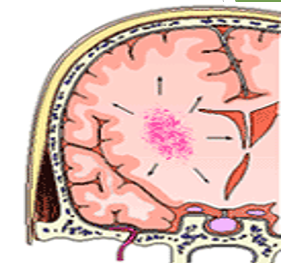

Closed head injury

A closed head injury occurs when a person receives a traumatic blow to the head without a facture or displacement to the skull.

Closed head injuries are quite dangerous because secondary swelling occurs within the brain, either from edema or bleeding. Resulting compression causes further injury (secondary injuries).

Brain swelling may manifest by liquid or brain tissue swelling through any available openings, including the eye sockets.

The brain is closed system with little room for edema uThe brain is a closed vault containing

ubrain tissue

ucerebral spinal fluid (CSF)

ublood supply.

uAny injury to the skull, brain tissue, arteries, or CSF causes cerebral swelling with accompanying blood pressure increases. This results in an increase in intracerebral pressure.